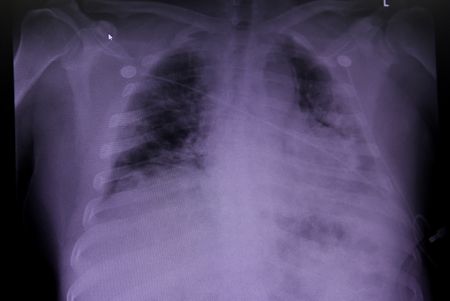

Traditional race-based equations for interpreting the results of spirometry, the most commonly used type of pulmonary function test, therefore grew from the idea that “normal” differs by race.

New, race-neutral equations for determining lung function – taking into account height, age and gender but not race – aim to help correct such inequities. The guideline advising use of race-neutral formulas was issued last year by the thoracic society.